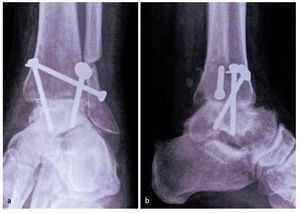

Fig. 13 Obtener radiografía anteroposterior y lateral intraoperatoria para comprobar la posición de los tornillos. Lavado y cierre de la herida con suturas absorbibles interrumpidas y con suturas no absorbibles para la piel. Vendaje compresivo estéril y férula por debajo de la rodilla. No se emplea drenaje de aspiración.

— Se debe evitar la colocación inadecuada de tornillos en otra posición que no sea un ángulo de 30 ° con el eje tibial. El punto de cruce debe ser proximal al pilón tibial ya que esto aumenta la estabilidad (fig. 13). Una posición inadecuada de los tornillos da lugar a más micromovimientos y, en consecuencia pone en riesgo la solidez de la fusión33.

Creemos que la construcción con 3 tornillos es biomecánicamente deseable cuando se utiliza una técnica de preparación de superficie con corte plano. Los tornillos colocados en paralelo producen mayores fuerzas de compresión. Sin embargo, puesto que se utilizan pinzas Weber para la compresión, nuestro objetivo es la construcción de tornillo más rígida. El uso de tornillos que se cruzan justo proximales a la superficie de fusión a un ángulo de 30º respecto al eje tibial ha demostrado ser superior para este fin10,15,33. Por lo tanto, la técnica descrita proporciona resultados fiables en seguimiento a largo plazo para una amplia gama de indicaciones de la artrodesis.